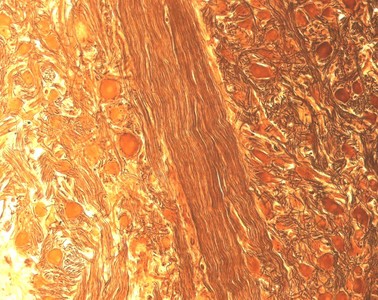

Präparat 27: Multipolare Nervenzellen, Grenzstrangganglion (Rind), Cajal-Versilberung

An diesem Präparat aus einem Ganglion des Grenzstrangs, Truncus sympathicus, sind die Nervenzellen mit der Cajal-Versilberung gefärbt (imprägniert). Wie Sie ja bereits bei Präparat 26 gelernt haben, besitzen Nervenzellen ein Perikaryon und unterschiedliche Fortsätze, die Dendriten und das Axon. Mit der Cajal-Versilberung werden Bestandteile des Zytoskeletts, die Neurofibrillen, tiefbraun bis schwarz angefärbt. Mit dem Elektronenmikroskop lassen sich Neurofibrillen in Neurofilamente und Neurotubuli auflösen. Die Neurofibrillen sind in den Axonen der Nervenzellen viel kompakter zusammengelagert als in den Dendriten und Perikaryen des Neurons. Die Axone erscheinen daher wesentlich dunkler als die Dendriten und die Perikaryen, die gelblich/braun gefärbt werden und nur am Rand versilberte Neurofibrillen zeigen. Der Zellkern der Neurone ist nicht angefärbt und erscheint daher als rundes helleres Gebilde im Perikaryon. Gliazellen (Satellitenzellen), die die Perikaryen umgeben, sind hier nicht eindeutig zu identifizieren.

Der Truncus sympathicus (Grenzstrang) ist Teil des vegetativen Nervensystems und liegt der Wirbelsäule an. Charakteristisch für ein vegetatives Ganglion sind zum einen die unterschiedlich großen, multipolaren Nervenzellen. Zum anderen ist die Lage der Gliazellen, welche die Perikarya der meisten Neurone im peripheren Nervensystem komplett einhüllen, in vegetativen Ganglien oft inkomplett.